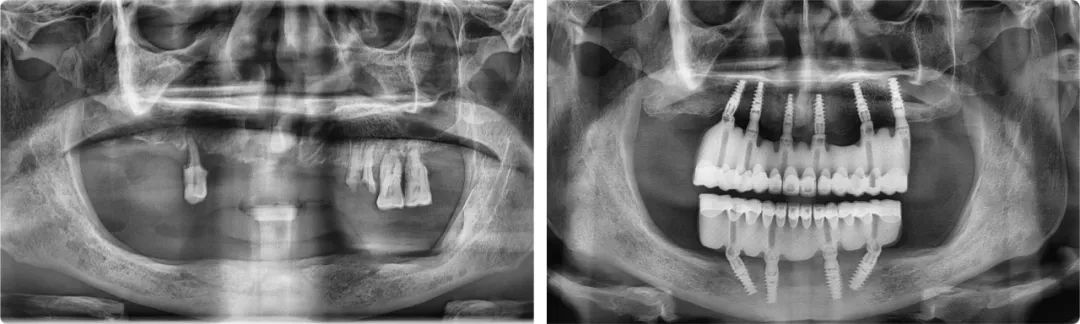

王旭東首例全口種植案例術前術后全景片